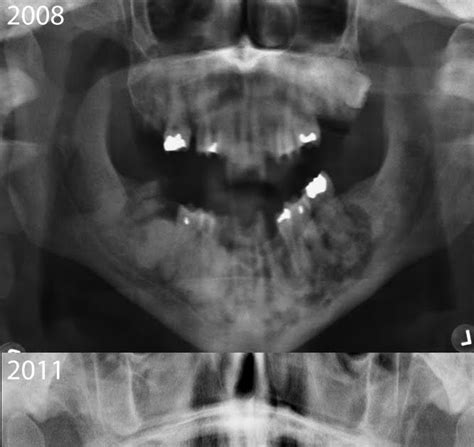

Practical oral radiology 2 2016

Practical oral radiology 2 2016 from image.slidesharecdn.com

Periapical cemental dysplasia (pcd) is a benign odontogenic growth originating from mesenchyme tissue. Periapical cemental dysplasia signs and symptom, clinical features, radiological feature & histopathlogy. Ileal pouch advancement for anorectal dysplasia or inflammation after restorative proctocolectomy. # difference between periapical granuloma and periapical cemental dysplasia: Cemental dysplasia is usually diagnosed during a regular check up appointment. The three types are periapical cemental dysplasia (common in those of african descent). Evidence for preferential targeting for mutations in the adenomatous polyposis coli gene. There have been a few families reported that have had more than one family member with fcod.

# difference between periapical granuloma and periapical cemental dysplasia: The three types are periapical cemental dysplasia (common in those of african descent). The correct answer is a. Шипулина ольга юрьевна, к.м.н., фбун «центральный нии эпидемиологии» роспотребнадзора. Ileal pouch advancement for anorectal dysplasia or inflammation after restorative proctocolectomy. The cellular morphology of carcinoma in situ and dysplasia or typical hyperplasia of the uterine cervix // cancer. Dysplasia — abnormal in form. Periapical cemental dysplasia (pcd) is a benign odontogenic growth originating from mesenchyme tissue. Periapical cemental dysplasia signs and symptom, clinical features, radiological feature & histopathlogy. Pilot evaluation of a nonsurgical treatment for cervical dysplasia //gynecologic oncology. Reagan j.w., seidermand i.l., saracusa y. Is a major player in the development of bronchopulmonary dysplasia? Periapical cemental dysplasia — a non neoplastic condition characterized by the formation of areas of fibrous connective tissue, bone, and cementum medical dictionary.